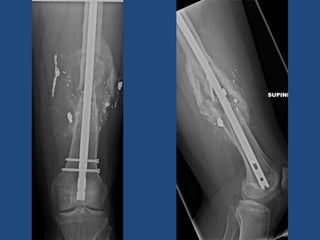

Femoral Intramedullary Nailing •Antegrade (Through hip) • Common, and can be used for all shaft fractures • Starting point options • Retrograde (Through knee) • Do not need fracture table • Bilateral femur fractures • Floating knee • Distal fracture

Retrograde Intramedullary nail